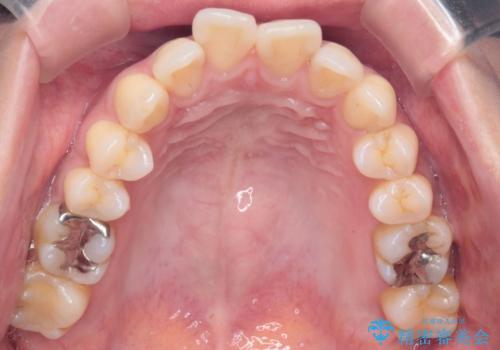

- 上の前歯の突出感を気にして来院された患者様です。

目立たない装置を希望とのことで、上顎左右第一小臼歯を抜歯し、インビザラインにて矯正治療を行うこととしました。